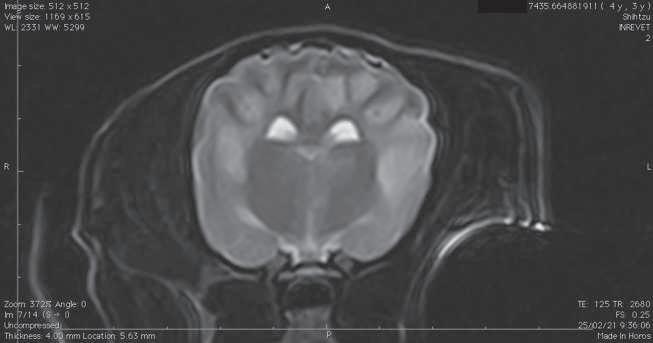

Figura 1. (A y C) Imágenes ponderadas en T2W. (B y D) FLAIR con lesiones hiperintensas en múltiples regiones encefálicas asociados a focos de edema con mayor evidencia en núcleos basales y tálamo (A, B) y lóbulos parietales y temporales (C y D).

A B C D

Figura 2. Imágenes ponderadas en T2W (A, C) y FLAIR (B, D) en las cuales se aprecia una disminución en las lesiones hiperintensas descritas en la figura 1.

Conbasealosresultadosderesonancia magnética (Figura 1), raza y hallazgos neurológicos los pacientes fueron diagnosticados con enfermedad inflamatoria cerebral (Meningoencefalitis de origen desconocido) e iniciaron con una terapia basadaenStee2020,10 conlacombinación decitarabina(Cytosar-U®Pfizer500mg) a dosis de 100/m2 y prednisona a dosis de 1 mg/kg iniciales por 4 semanas (dosis reducción a 36 semanas), para posteriormente evaluar la evolución clínica del paciente y por imagen con las mismas indicaciones de resonancia previamente descritas.

En el presente estudio 5 de 6 pacientes mostraronunamejoracínicasignificativa, enunpaciente(Shih-tzu)elcualingresóen estatus epiléptico no presentó más crisis convulsivas ni se han reportado hasta el momento, el estado mental de los 6 pacientes mejoró de forma significativa, sólounpaciente(Yorkshire)conimágenes por resonancia magnética con herniación subfalcina continuó con giros, los déficits propioceptivos continuaron en 2 de 6 pacientes (Cuadro 3). En las imágenes por resonancia magnética posterior a las 4 semanas iniciado el tratamiento se vio unadisminucióndeledemareportadoque va desde el 85% hasta 50% (Figura 2).